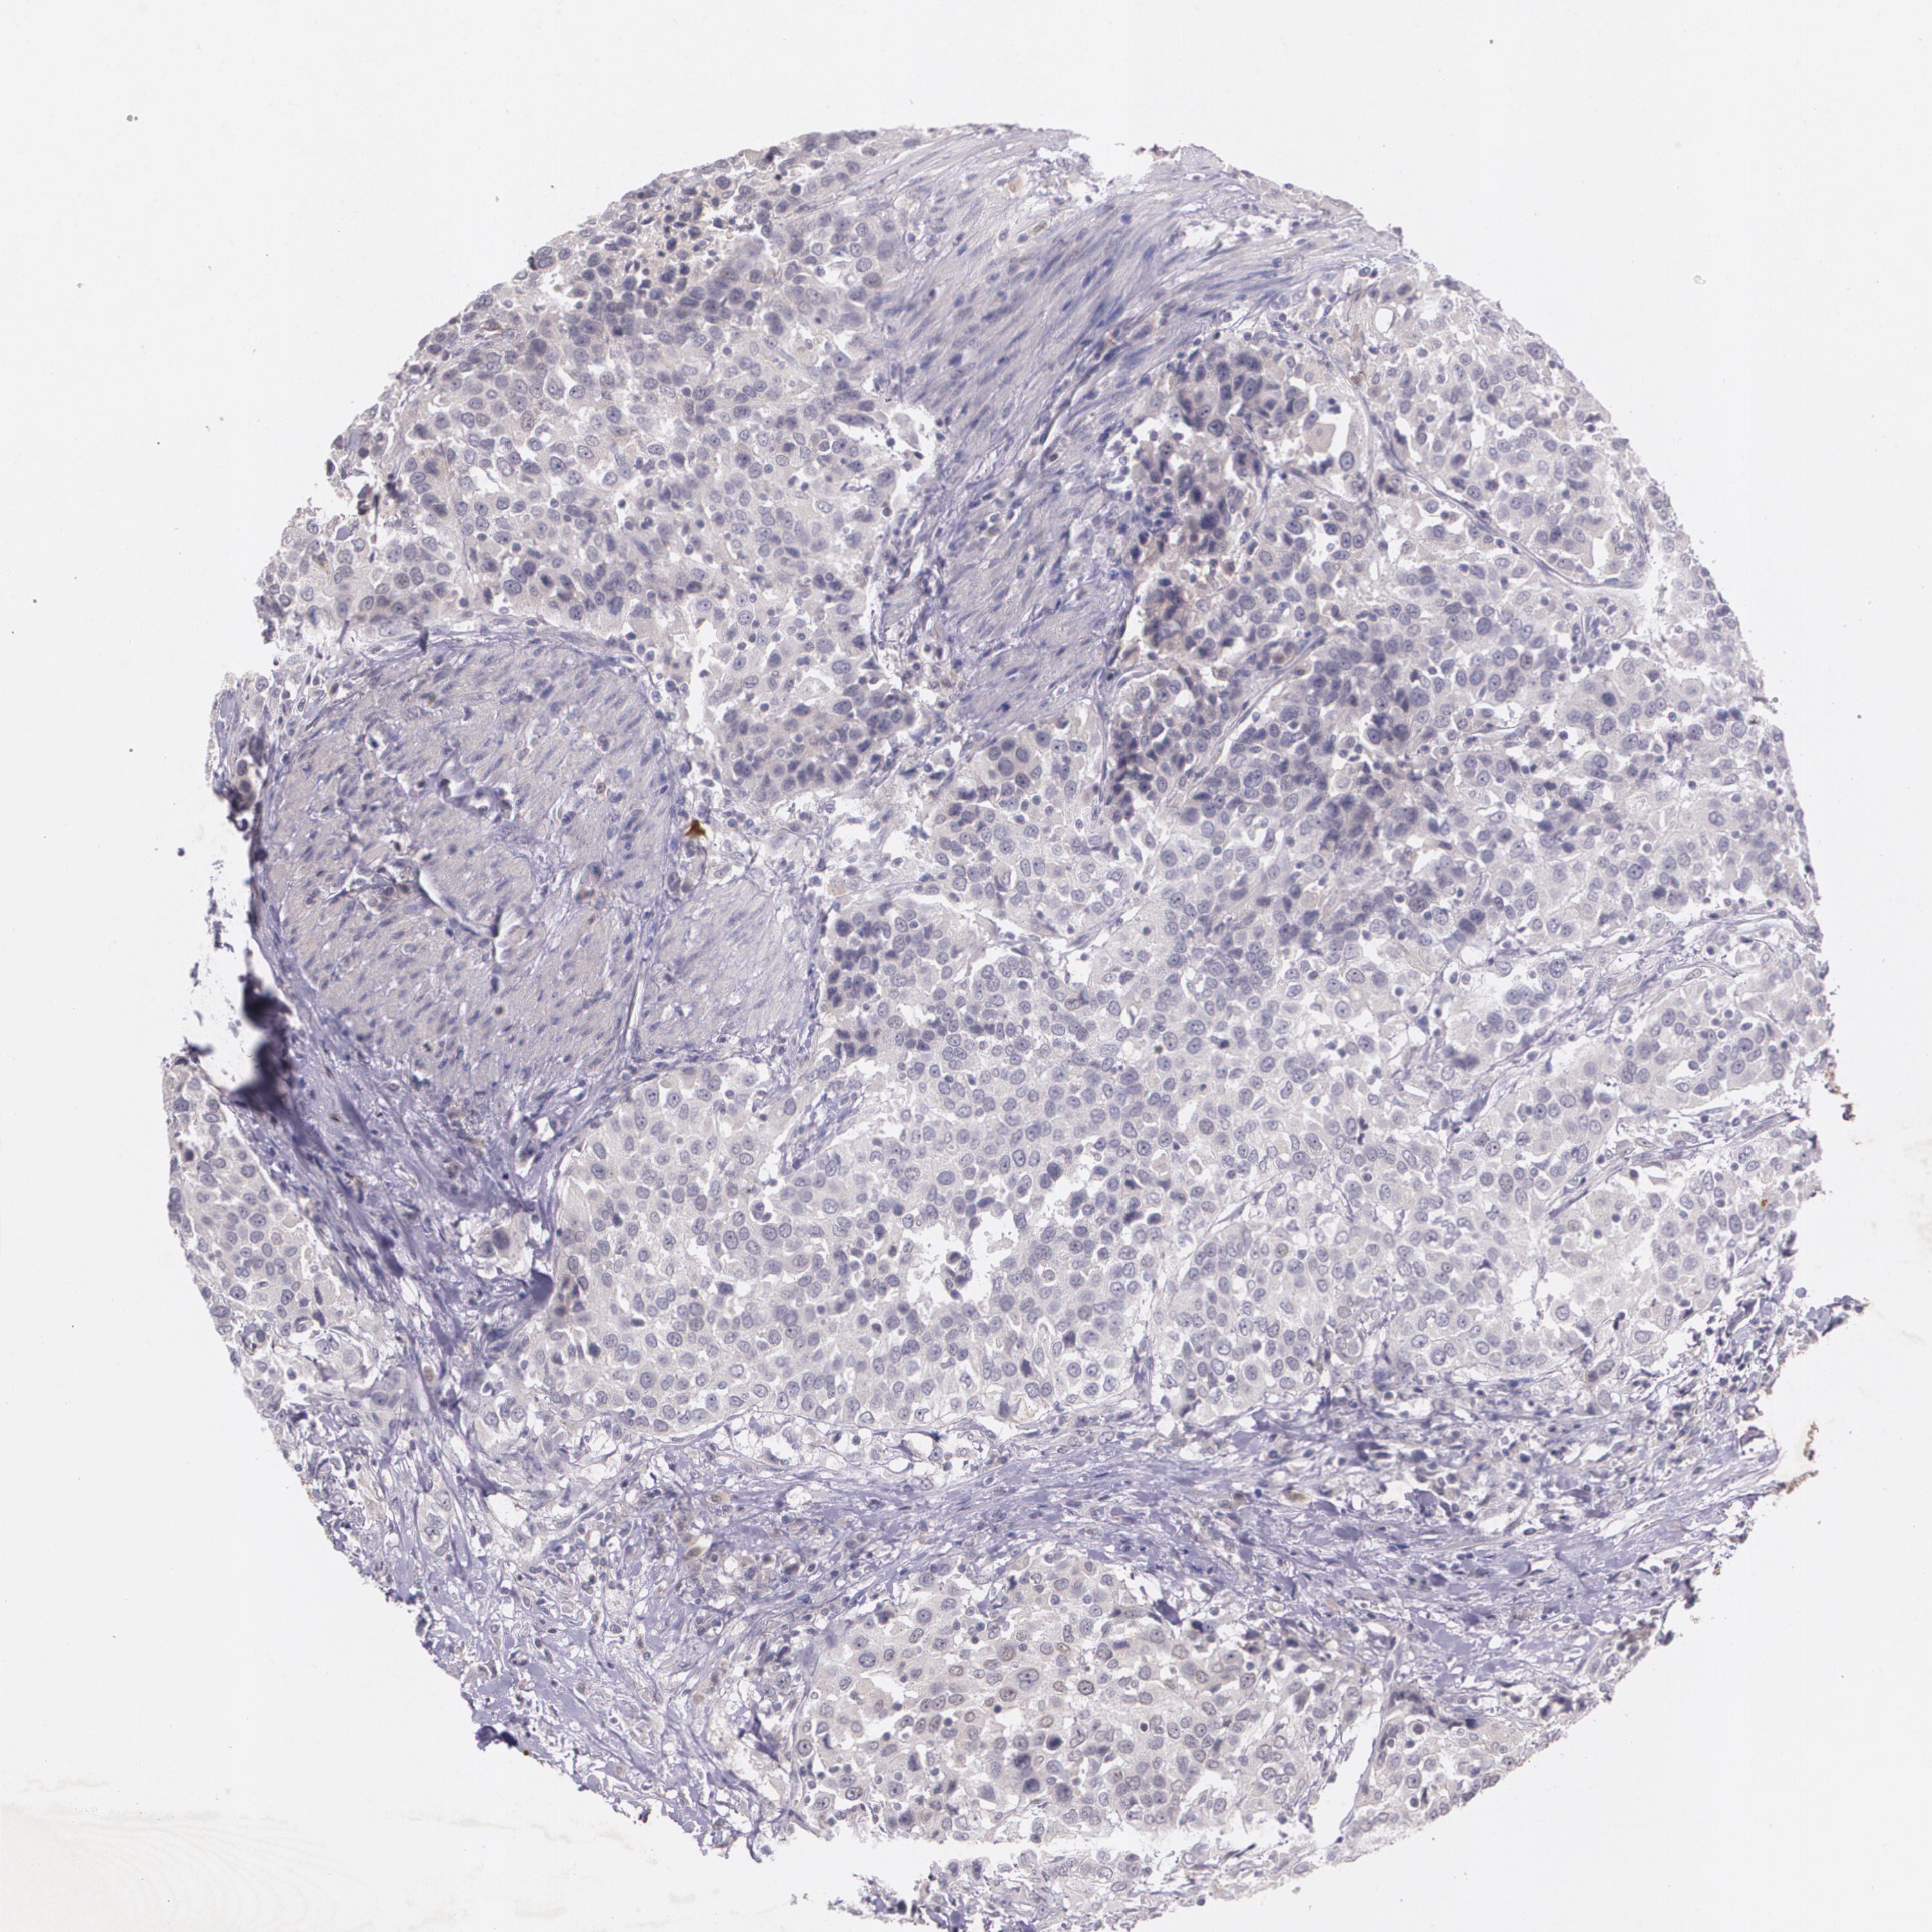

UROTHELIAL CANCER - Protein expressioni

A mouse-over function shows sample information and annotation data. Click on an image to view it in a full screen mode. Samples can be filtered based on level of antibody staining by selecting one or several of the following categories: high, medium, low and not detected. The assay and annotation is described here.

Note that samples used for immunohistochemistry by the Human Protein Atlas do not correspond to samples in the TCGA dataset.

Antibody stainingi

Antibody staining in the annotated cell types in the current human tissue is reported as not detected, low, medium, or high, based on conventional immunohistochemistry profiling in selected tissues. This score is based on the combination of the staining intensity and fraction of stained cells.

Each image is clickable and will lead to virtual microscopy that enables deeper exploration of all samples and also displays staining intensity scores, fraction scores and subcellular localization as well as patient and tissue information for each sample.

Antibody HPA002823

Antibody CAB002760

Staining

High

Medium

Low

Not detected

Intensity

Strong

Moderate

Weak

Negative

Quantity

>75%

75%-25%

<25%

None

Location

Nuclear

Cytoplasmic/membranous

Cytoplasmic/membranous,nuclear

Urothelial carcinoma, High grade

Urothelial carcinoma, Low grade

Adenocarcinoma, NOS